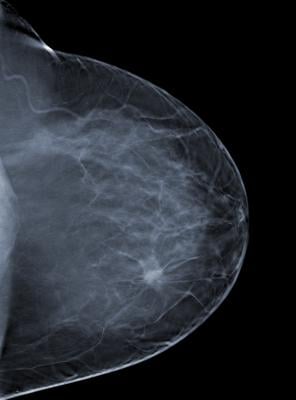

May 1, 2017 — Breast cancers detected by mammography screening do not spontaneously disappear or regress if left untreated, according to a new study published in the Journal of the American College of Radiology (JACR). The scientific findings contradict claims that many cancers found via mammography may simply “go away” if left undiscovered or untreated.

Among all practices involved in the study, 25,281 screen-detected invasive breast cancers and 9,360 cases of screen-detected ductal carcinoma in situ were reported over the 10-year study period. Among these cancers, there were 240 cases of untreated invasive breast cancer and 239 cases of untreated ductal carcinoma in situ. None were reported to have spontaneously disappeared or regressed at next mammography.

An unknown percentage of these 479 cases represent overdiagnosis, but because all untreated screen-detected cancers were visible and suspicious for malignancy at next mammographic examination, delaying the onset of screening (from age 40 to ages 45 or 50) or increasing the interval between screenings (biennial vs annual) should not reduce the frequency of overdiagnosis.

Medical science cannot yet determine which cancers will or will not advance to kill the person afflicted.